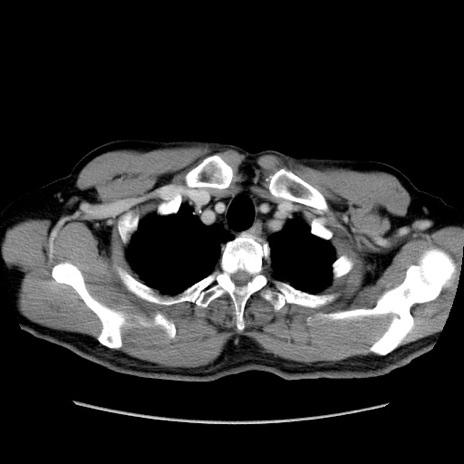

症例34(横断像)

【症例】60歳代 男性

【主訴】右鼠径部膨隆

【現病歴】1年程前より右鼠径部膨隆あり。自己にて還納可能だったため放置していた。3時間前より右鼠径部の脱出を認め、還納困難となり受診。

【既往歴】高血圧

【身体所見】右鼠径部に小児頭大の膨隆あり。弾性硬であり、用手還納は困難。左鼠径部にも膨隆を認める。脱出はなし。